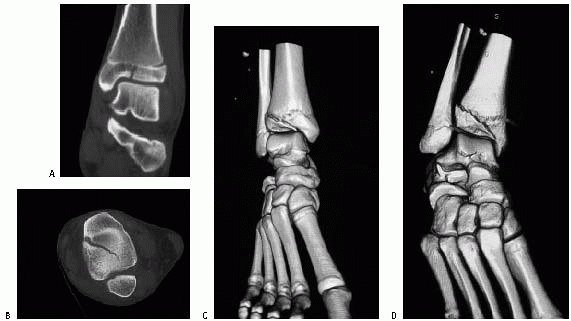

The anterior and posterior inferior tibiofibular ligaments course

inferiorly from the anterior and posterior surfaces of the distal

lateral tibia to the anterior and posterior surfaces of the lateral

malleolus. The anterior ligament is important in the pathomechanics of

“transitional” ankle fractures. Just anterior to the posteroinferior

tibiofibular ligament is the broad, thick inferior transverse ligament,

which extends down from the lateral malleolus along the posterior

border of the articular surface of the tibia, almost to the medial

malleolus. This ligament serves as a part of the articular surface for

the talus. Between the anterior and posterior inferior tibiofibular

ligaments, the tibia and fibula are bound by the interosseous ligament,

which is continuous with the interosseous membrane above. This ligament

may be important in the pathomechanics of what we have termed incisural

fractures.

This ligament arises from the medial malleolus and divides into

superficial and deep layers. Three parts of the superficial layer are

identified by their attachments: tibionavicular, calcaneotibial, and

posterior talotibial ligaments. The deep layer is known as the anterior

talotibial ligament, again reflecting its insertion and origin. On the

lateral side, the anterior and posterior talofibular ligament, with the

calcaneofibular ligaments, make up the lateral collateral ligament (see

Fig. 26-28).

![]() |

|

FIGURE 26-28 Lateral view of the ankle demonstrating the anterior and posterior talofibular ligaments and the calcaneofibular ligament.